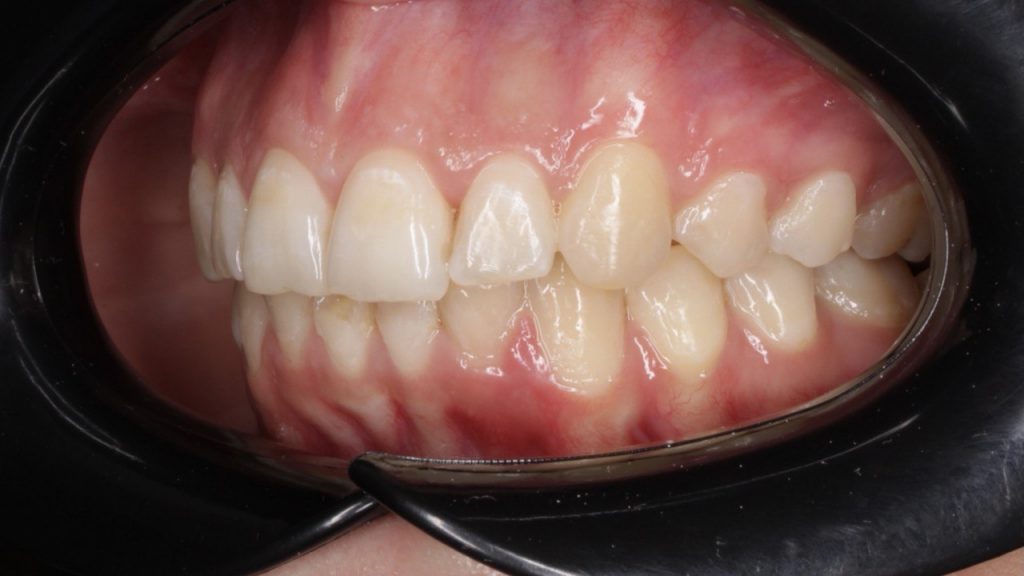

Портфолио - после 3